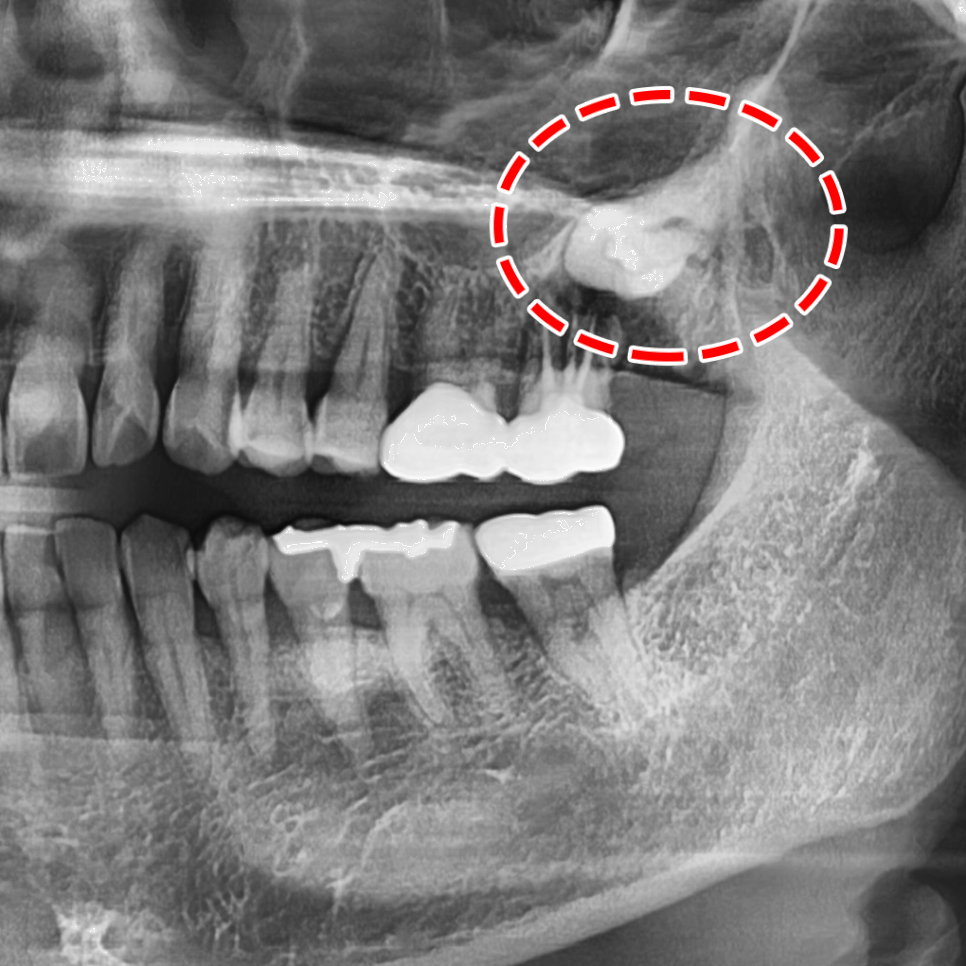

사랑니 발치는 사전에 정확한 검사를 통해

섬세한 계획을 수립하고 나서 이뤄지는데요.

특히 위쪽은 상악동을,

아래쪽은 신경을 주의해야 됩니다.

이를 뽑는 과정에서 잘못 건드렸다가 상악동 천공

또는 신경을 건드려 일시적인 마비 증상이 나타날 수 있습니다.

그러므로 치근(치아의 뿌리)과

상악동막, 신경과의 거리가 얼마나 되는지

세밀한 분석이 이뤄져야 됩니다.

연세다감치과에서는 3D CT 촬영을 통해

위의 사항을 고려하여 안전하고 빠르게 뽑을 수 있게

꼼꼼히 계획을 수립하여 치료를 시작합니다.